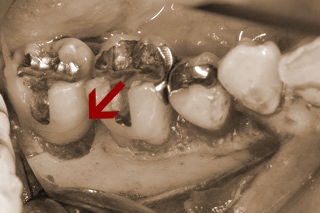

向かって右奥歯の根が露出してしまっています。

噛み合わせや不適切な治療や歯ブラシの仕方によって、歯周病が進行しきった状態です。

こうなってしまうと残念ながら救う手だてはありません。

前方の歯の詰め物、被せ物も決して精度高い治療とは言えません。歯周病は早期発見・早期治療が大切なのです。